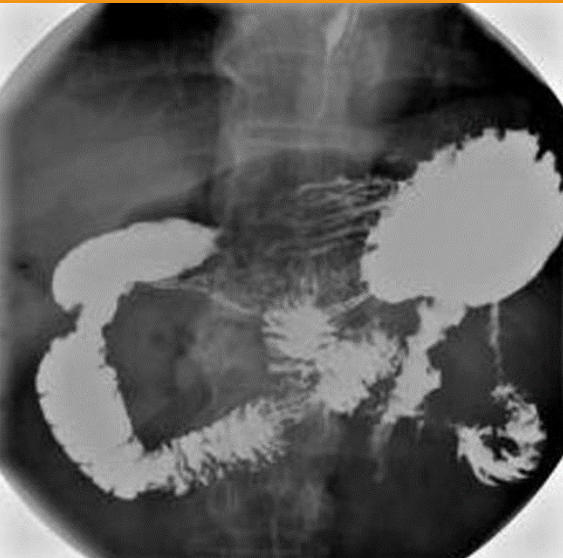

1)What does single contrast mean in the first image?

2)What does double contrast mean in the 2nd image?

3)contrast media used for this examination?

4)the 3 contraindications of the contrast used?

1)entire colon is filled only with barium sulfate (this is a BE)

2)both barium sulfate and air. (this is a ACBE)

3)Barium Sulfate

4)DON’T us if suspected bowel perforation; Bowel obstruction (high risk of retention or perforation);

Pre- or post-surgy